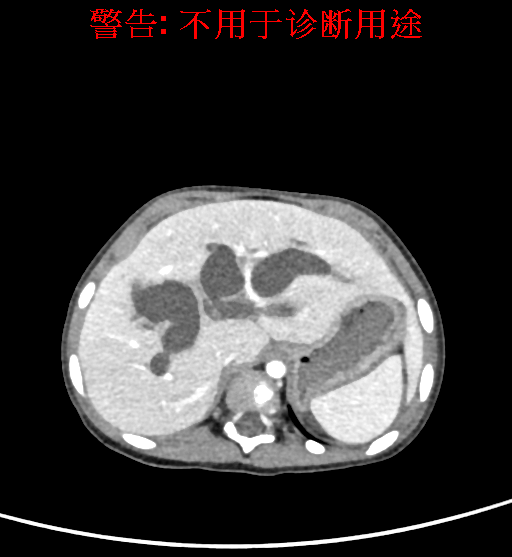

实验室检查: 血常规:血常规:WBC 11.49*109/L,NEU3.60*109/L,RBC4.36*1012/L,HB 119g/L, PLT 411*109/L,MCHC 318.0g/L, PCT 0.45%, RET% 1.64% 生化全套:ALT 18.00 U/L, AST 44.00 U/L, ALT/AST 0.41, ALB 47.35g/L,BIL-T 6.60 umol/L, BIT-D 2.68 umol/L, BUN 4.80 mmol/L, CREA 18.00 umol/L 肝炎全套: 炎症反应标志物: 诊疗过程: CT结果输入海信CAS系统后行3D重建及手术规划后,于2018-6-7全麻下行“胆囊切除+胆总管囊肿切除+肝总管空肠吻合术”手术治疗: 术前三维重建及手术方案设计: 将0.625mm双源薄层CT资料的静脉期和动脉期Dicom格式文件导入海信CAS系统。 通过调节窗宽窗位调整CT序号,对肝实质,胆囊,下腔静脉,肿瘤,肝动脉、门静脉及肝静脉等进行三维重建;系统自动计算肝脏体积,肝脏体积为383.8ml,通过术前模拟手术,精准判断手术切除范围,进行精密术前规划及讨论后实施手术。 手术步骤: 麻醉成功后,患儿取平卧位,2.5%碘伏消毒手术区皮肤,铺无菌巾单。取右上腹纵口长约5m,切开皮肤、皮下织组,腹直肌前鞘、腹直肌,后鞘和腹膜。探查见:胆总管3×2cm大小,胆囊管迂曲,长约10cm。剥离、切除胆囊,游离胆总管,将之横断:①近端即肝总管,剪裁后被吻合用;②远端游离切除囊肿内壁,直至胆总管开口于十二指肠处,冲洗后予以结扎缝扎。距treits韧带20cm处横断空肠:①近端与其远端25cm处的空肠侧壁行端侧双层吻合,吻合口通畅;②远端断端封闭,其侧壁剪开,并经横结肠后提至肝门处,与剪裁的肝总管行端侧双层吻合。缝合修补胆囊床及系膜裂孔,肝门部放置橡胶引流管一根。温盐水冲洗腹腔。检查无活动性出血,清点纱布器械无误,依次缝合腹壁各层。手术顺利,麻醉满意,出血不多,未输血,术后病人先进入麻醉恢复室,苏醒后回病房。手术时术者可开启Hisense CAS系统手势控制功能,对肝脏及胆囊解剖结构进行实时、全方观察、评估,起到术中导航作用。 术后病理: 1. (囊肿壁)囊肿性病变,囊壁构成于增生的纤维组织呈慢性炎,内衬假复层柱状上皮,囊壁内见较多增生的腺体。请结合临床。 2. 慢性胆囊炎。 随访情况: 患儿术后2周恢复良好 术前CT检查:动脉期

平衡期